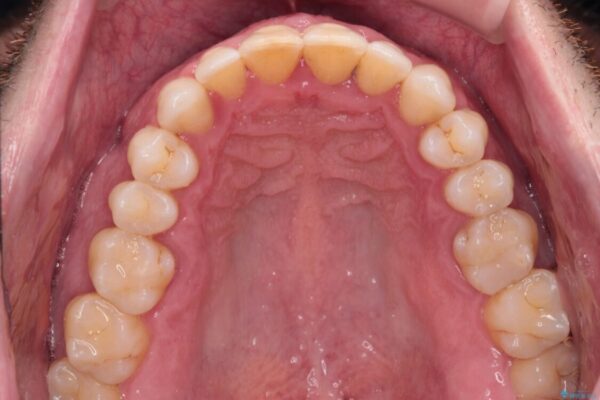

治療前

• 前歯でものを噛みきりたい 目立たない装置でのワイヤー矯正 治療前画像

以前矯正治療を経験されたそうですが、舌の突出癖により上下前歯に隙間ができている様子でした。

前歯の非接触改善は、インビザラインの得意とするところですが、マウスピース矯正は絶対に継続できないとのことで、ワイヤー装置にて矯正治療を行うこととしました。